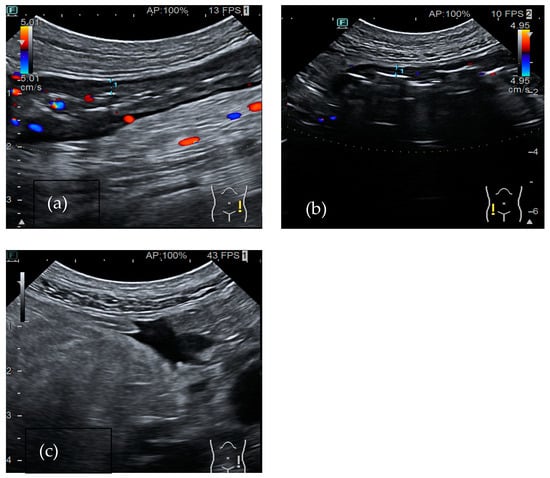

Clostridium difficile

Clostridium difficile (CD) is an anaerobic, Gram-positive, spore-forming bacillus that represents a leading cause of antibiotic-associated diarrhea. It produces two main exotoxins, toxin A and toxin B, which can harm colon epithelium and trigger an inflammatory reaction. It may lead to mucosal necrosis and the formation of pseudomembranes, which consist of an inflammatory exudate covering the exposed mucosa [49,50]. The diagnosis of the disease consists of the detection of toxins in the stool, but radiological exams also supply useful information about the infection. In particular, a CT scan is the most sensitive examination to define colon extension. In most cases, it shows pancolitis with mural thickening, even if infections limited to focal parts of the colon have also been described [51]. Moreover, a CT scan may also reveal contrast material appearing between pseudomembranes and ascites, known as the “accordion sign”. In bowel ultrasound, the wall of the large bowel appears thickened between 6 and 20 mm (Figure 2). It often shows submucosal and mucosal edema, which is represented by a heterogeneous intermediate-echogenicity band, with preservation of the muscular layer [52]. Moreover, suppurating ulcers may appear as hypoechoic defects in the hyperechoic interface between mucosa and lumen. In severe cases coalescent pseudomembranes appear as linear echogenic structures parallel to the mucosal interface [53]. Ascites is also present more commonly than in IBD, which is probably related to hypoalbuminemia and increased bowel permeability. In 2015, a case–control study compared the presence of five ultrasonographic features (colon thickness, internal and external ring, large bowel content diminution, and ascites) in patients who were hospitalized with diarrhea. The study group was toxin-positive, while the control group was toxin-negative. The colonic wall thickening was present in 91% (n = 61) of patients with CD toxin, while it was present in only 21% (n = 15) of control group. This feature had high negative and positive predictive values for Clostridium difficile infection (CDI), and the authors concluded it may help in confirming or excluding the diagnosis of CDI. Furthermore, the other ultrasound parameters had high positive predictive values and may help to confirm CDI [54]. Therefore, even if none of these findings are pathognomonic, performing bowel ultrasound is a useful tool in an acute setting, especially in patients with kidney disfunction.

Figure 2.

A 36 year-old-woman with Clostridium diarrhea. Bowel ultrasound showed colon wall thickening (a) that normalized after adequate treatment (b).